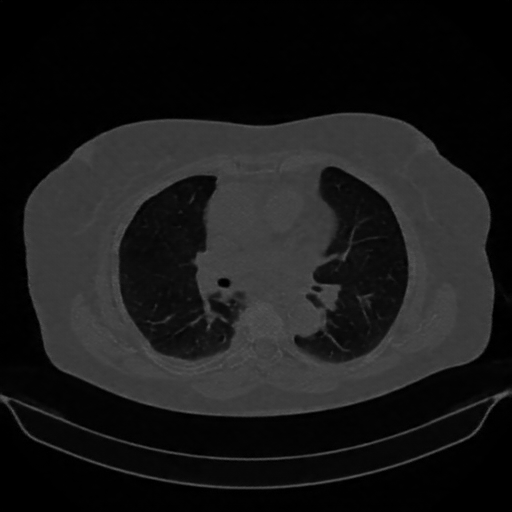

Reconstructed NATIVE CT scan (cycle consistency)

No window - Raw intensity values

Lung window (WL -600, WW 1500 β†’ Low βˆ’1350, High +150)

Mediastinum window (WL 40, WW 400 β†’ Low βˆ’160, High +240)